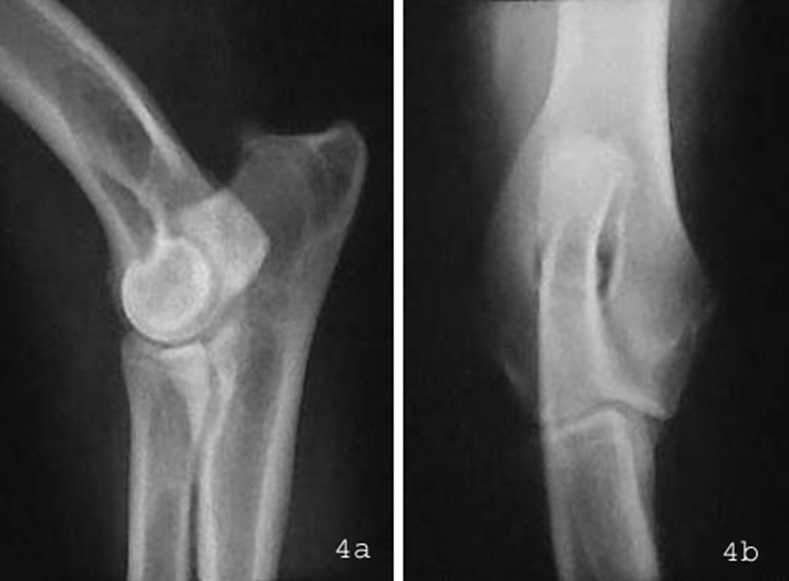

Röntgen

Zur Eingrenzung der klinischen Verdachtsdiagnose muß eine Röntgenuntersuchung des betroffenen Ellbogengelenks durchgeführt werden, wobei grundsätzlich beide Ellbogengelenke vergleichend in mindestens zwei Ebenen geröntgt werden sollten. Die Röntgendiagnostik des FPC ist jedoch oft sehr schwierig, da der Processus coronoideus medialis der Ulna von anderen Knochenstrukturen überlagert wird (Abb.4).

Abbildung 4: Röntgenaufnahmen von einem gesunden rechten Ellbogengelenk in (a) seitlichem (medio-lateral) Strahlengang und (b) von vorne (kranio-kaudal). Der Bereich des Processus coronoideus medialis der Ulna (Kreis) ist von anderen Knochenstrukturen überlagert